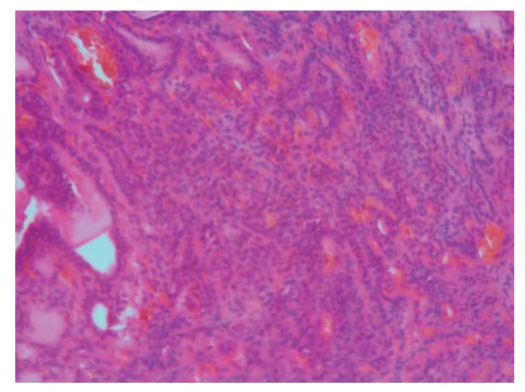

1. Fig. 1. Results of histological examination. Solid alveolar region of the medullary thyroid cancer (× 20).